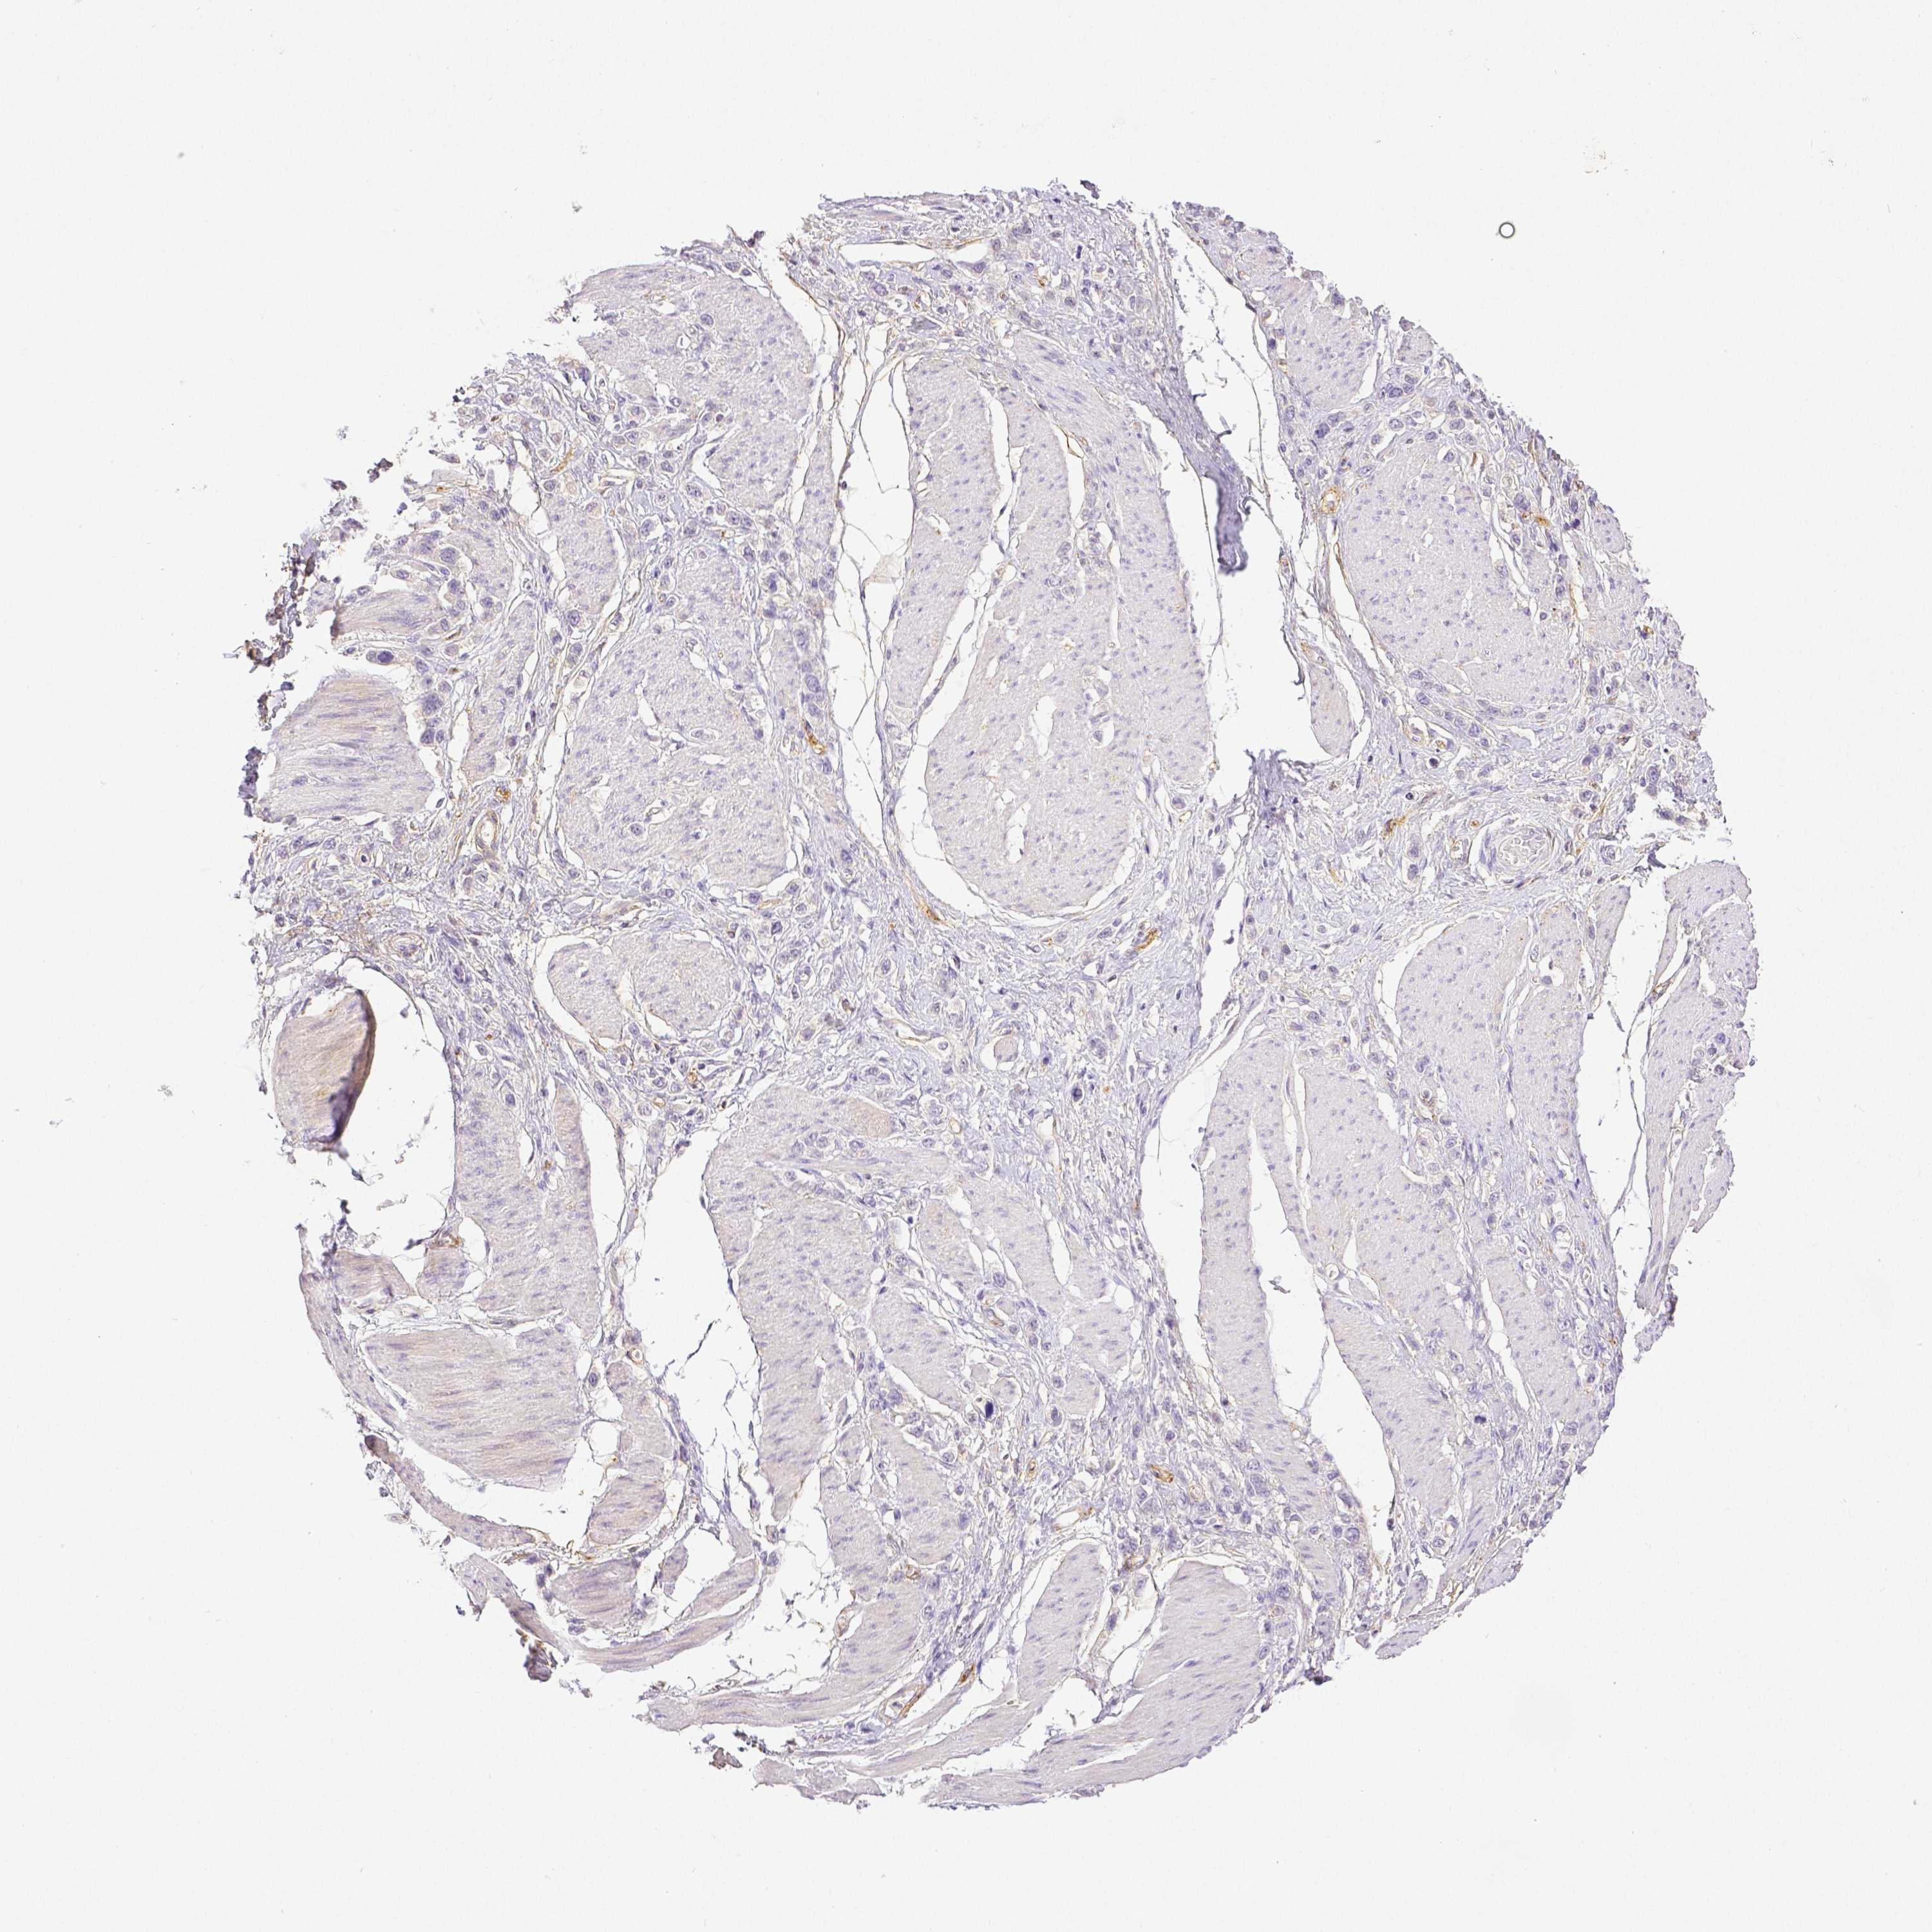

STOMACH CANCER - Protein expressioni

A mouse-over function shows sample information and annotation data. Click on an image to view it in a full screen mode. Samples can be filtered based on level of antibody staining by selecting one or several of the following categories: high, medium, low and not detected. The assay and annotation is described here.

Note that samples used for immunohistochemistry by the Human Protein Atlas do not correspond to samples in the TCGA dataset.

Antibody stainingi

Antibody staining in the annotated cell types in the current human tissue is reported as not detected, low, medium, or high, based on conventional immunohistochemistry profiling in selected tissues. This score is based on the combination of the staining intensity and fraction of stained cells.

Each image is clickable and will lead to virtual microscopy that enables deeper exploration of all samples and also displays staining intensity scores, fraction scores and subcellular localization as well as patient and tissue information for each sample.

Antibody HPA003733

Antibody CAB068243

Antibody CAB068244

Adenocarcinoma, NOS